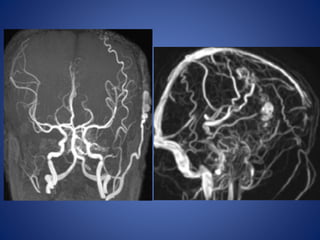

5 yrs male child with history of left sided focal seizures with secondary generalization

5 yrs malechild with history of left sided focal seizures with secondary generalization

Moya Moya • Chronicprogressive arteriopathy of unknown cause and has become one of the most common causes of pediatric stroke. • Suzuki and Kodama classified the evolution of moyamoya disease using angiographic findings to define six phases of the disease: Stage 1- Narrowing of carotid fork. Stage 2- Initiation of basal moyamoya. Stage 3- Intensification of moyamoya Stage 4- Minimization of moyamoya. Stage 5- Reduction of moyamoya . Stage 6- Disappearance of moyamoya.

• Stenosis/occlusion ofthe distal ICA • moyamoya vessels with signal voids in the basal ganglia • ischemia • infarction • atrophy, and ventriculomegaly. • Small abnormal net-like vessels proliferate giving "puff of smoke" appearance. • Contrast-enhanced T1WI - marked leptomeningeal enhancement along the cortical sulci (ivy sign). often show contrast stagnating in slow-flowing collateral vessels both in the brain parenchymal and over its surface. MR imaging